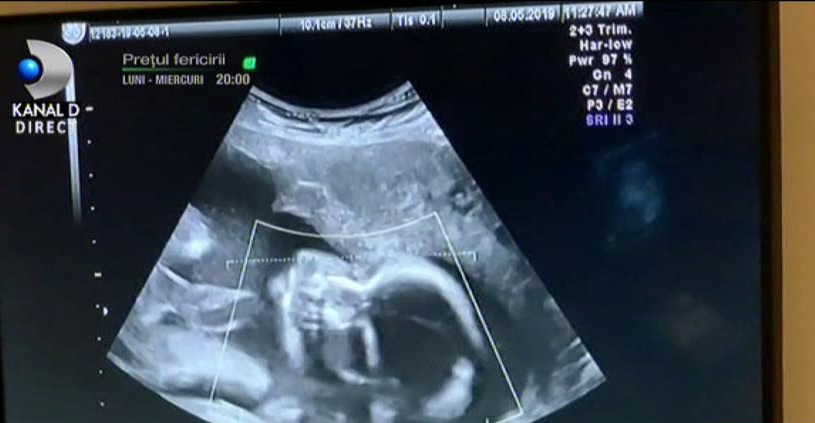

Anca Serea și Adi Sînă au filmat momentul în care au mers la ecografie și au văzut-o pe micuța Leah.

Anca Serea a avut mari emoții înainte de a ajunge la clinică și a o vedea pe monitor pe bebelușa din burtică, cel de-al șaselea copil al său.

Emoționată, dar fericită, Anca Serea a răsuflat ușurată atunci când a aflat că totul este în regulă cu fetița ei, care va primi numele Leah.

"Seamănă cu Ava și cu frații ei. Uite ce năsuc are! Mami e foarte fericită, avea mari emoții. Totul e bine, o să venim la consultație peste o lună. Până atunci trebuie să fim fete cumințele", a spus Anca Serea în vlog.